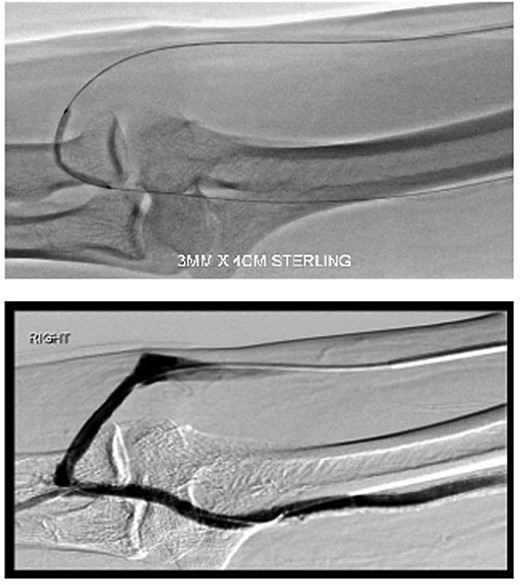

The harvested vein was tunnelled between the proximal radial artery (at the brachial bifurcation) and the elbow segment of the AVF. The AVF was then ligated at the anastomosis. A thrill was well felt in the upper arm after the procedure (Fig. 4).

Post-operatively, all symptoms of ischaemia resolved (Fig. 5). The patient’s pulses were restored and dialysis resumed without complications. A gentle angioplasty of the conduit vessel was performed 1 month later to maintain access flow (Fig. 6). The access site remained functional at the 12-month follow-up.